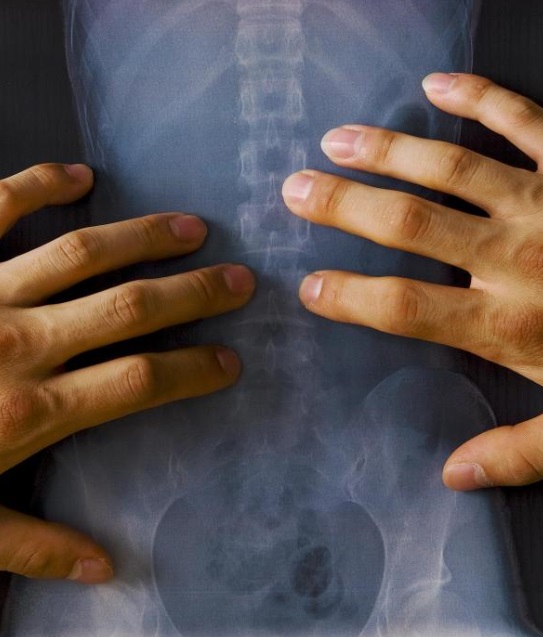

디스크 내장증은 디스크 내부가 손상돼 통증이 생기는 질환이다./사진=헬스조선DB

보통 허리가 아프면 허리 디스크라고 생각하기 쉬우나, 엑스레이를 찍어도 문제가 없다면 디스크 내장증을 의심해야 한다. 디스크 내장증은 노화가 아닌 무리한 신체 활동 등으로 생겨, 젊은 층도 취약하다.

디스크내장증은 엑스레이를 찍어도 쉽게 확인되지 않아 발견이 어렵다. 이때는 자기공명영상(MRI)을 촬영해야 한다. 디스크 내장증이 있으면 손상부위가 검게 보이는데, 정확한 진단을 위해선 디스크 내 약품을 삽입하는 추간판 조영술을 해야 한다. 디스크 내장증 초기에는 물리치료·약물치료와 운동 등 비수술적인 방법으로 치료할 수 있다. 비수술적 치료의 효과가 미비하다면, 디스크 내 열 치료술이나 융합술을 한다. 디스크 내 열 치료술은 디스크 내에 바늘을 삽입해 열로 신경을 치료하는 수술이고, 융합술은 손상된 디스크를 제거하고 인공 디스크를 삽입하는 수술이다. 평소 허리에 무리를 주지 않는 생활습관을 가져 디스크 내장증을 예방할 수 있다. 앉을 땐 허리를 곧게 펴고 다리를 꼬지 않아야 한다. 무거운 물건을 들을 땐 허리를 굽히고 몸과 물건을 최대한 가까이 붙여야 허리에 자극이 덜 간다. 과격한 운동 전 스트레칭을 충분히 하고 무리한 신체 활동을 자제하는 게 좋다.